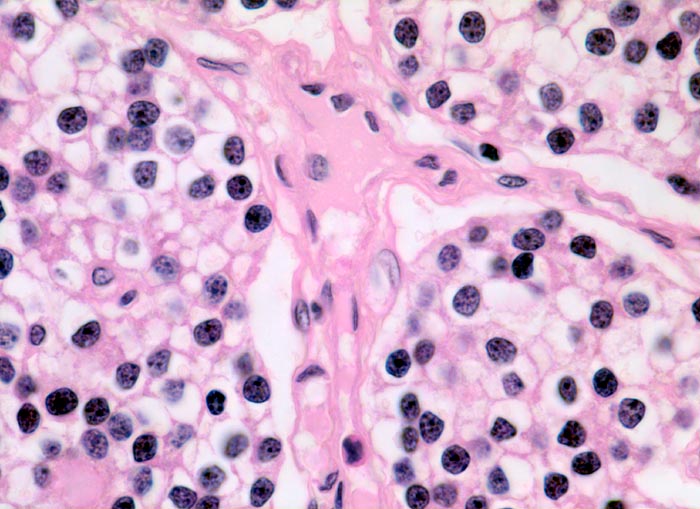

• Hyperplasie lipidarmer Hauptzellen.

• Areale mit oxyphilen Zellen.

• Verminderter Fettgehalt (<<35%). Für normale Nebenschilddrüsen gilt: